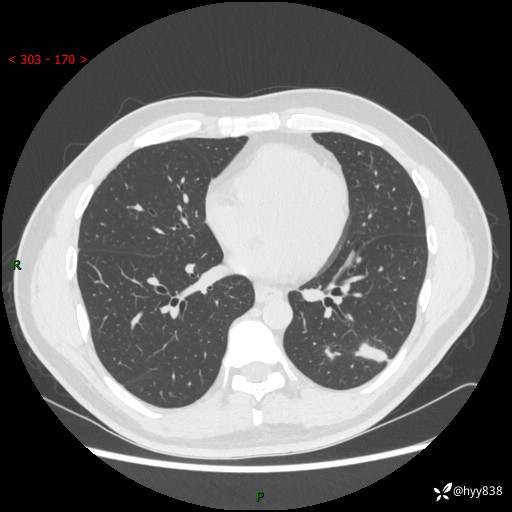

中年男性,胸闷3月余。多发团片、肺小叶分布、空气支气管征、明显强化---结果公布~

现病史:患者3月前出现胸闷,卧位时加重,坐位时缓解,无咽痛、咳嗽,无头痛,无全身酸痛,无结膜充血,无胸痛、心慌,无咯血,无呼吸困难,无咳痰,2024-07-02于当地市第一民医院行胸部CT,结果不详,2024-07-05就诊于我院急诊内科,行胸部CT同时增强,结果示:左肺下叶多发结节灶,考虑感染可能。今患者为求进一步诊治来我院,门诊以“肺部感染”收入我科。 患者本次起病来精神、食欲、睡眠尚可,大小便可,体力,体重无明显变化。

胸部CT平扫+增强

各期CT值:30hu 90hu 77hu